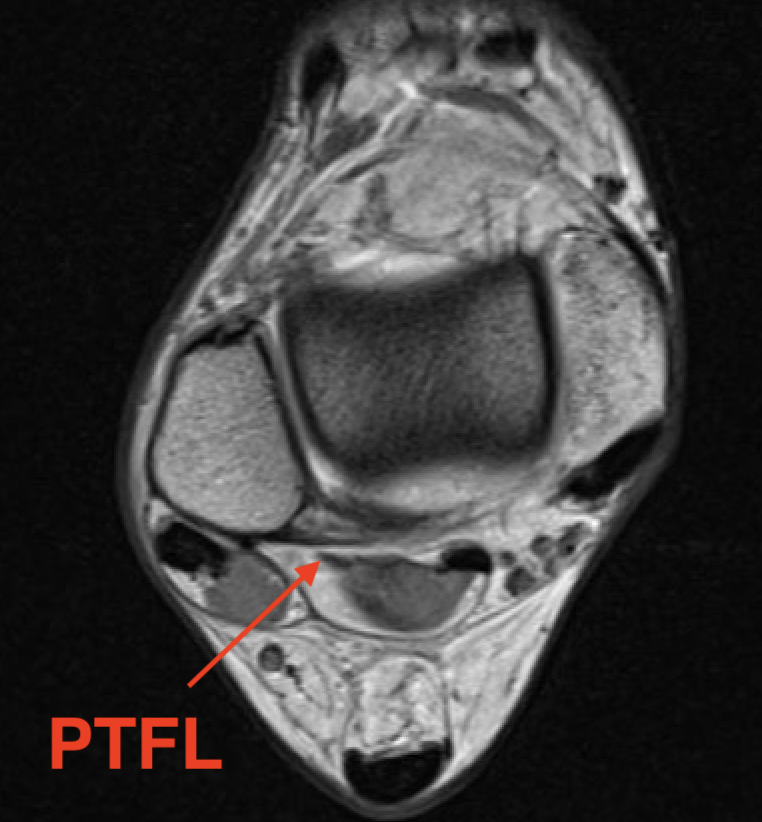

PTFL